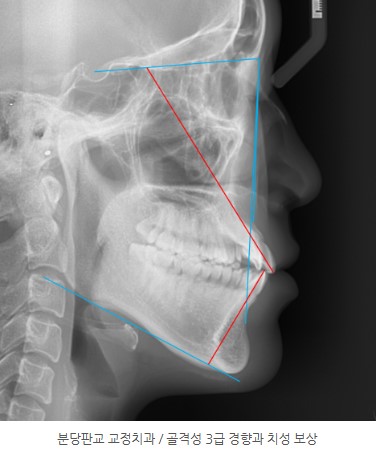

초진 상태 – 3급 부정교합 + 치성 보상이 겹쳐 있던 케이스

초진에서 확인된 주요 특징은 다음과 같습니다.

총생의 정도와 상악 전치의 각도를 고려하면 정석적으로는 발치 교정이 적합한 케이스였습니다.

특히 골격성 3급에서는

치성 보상(dental compensation) 양상이 흔합니다.

이 환자분 역시 이미 상악 전치의 각도가 커져 있어 미리부터 “뻐드러져 보이는” 느낌을 주는 상태였습니다.

골격성 3급 부정교합 + 장안모

중등도 총생과 3급 견치·구치 관계

상악 중심선 편위